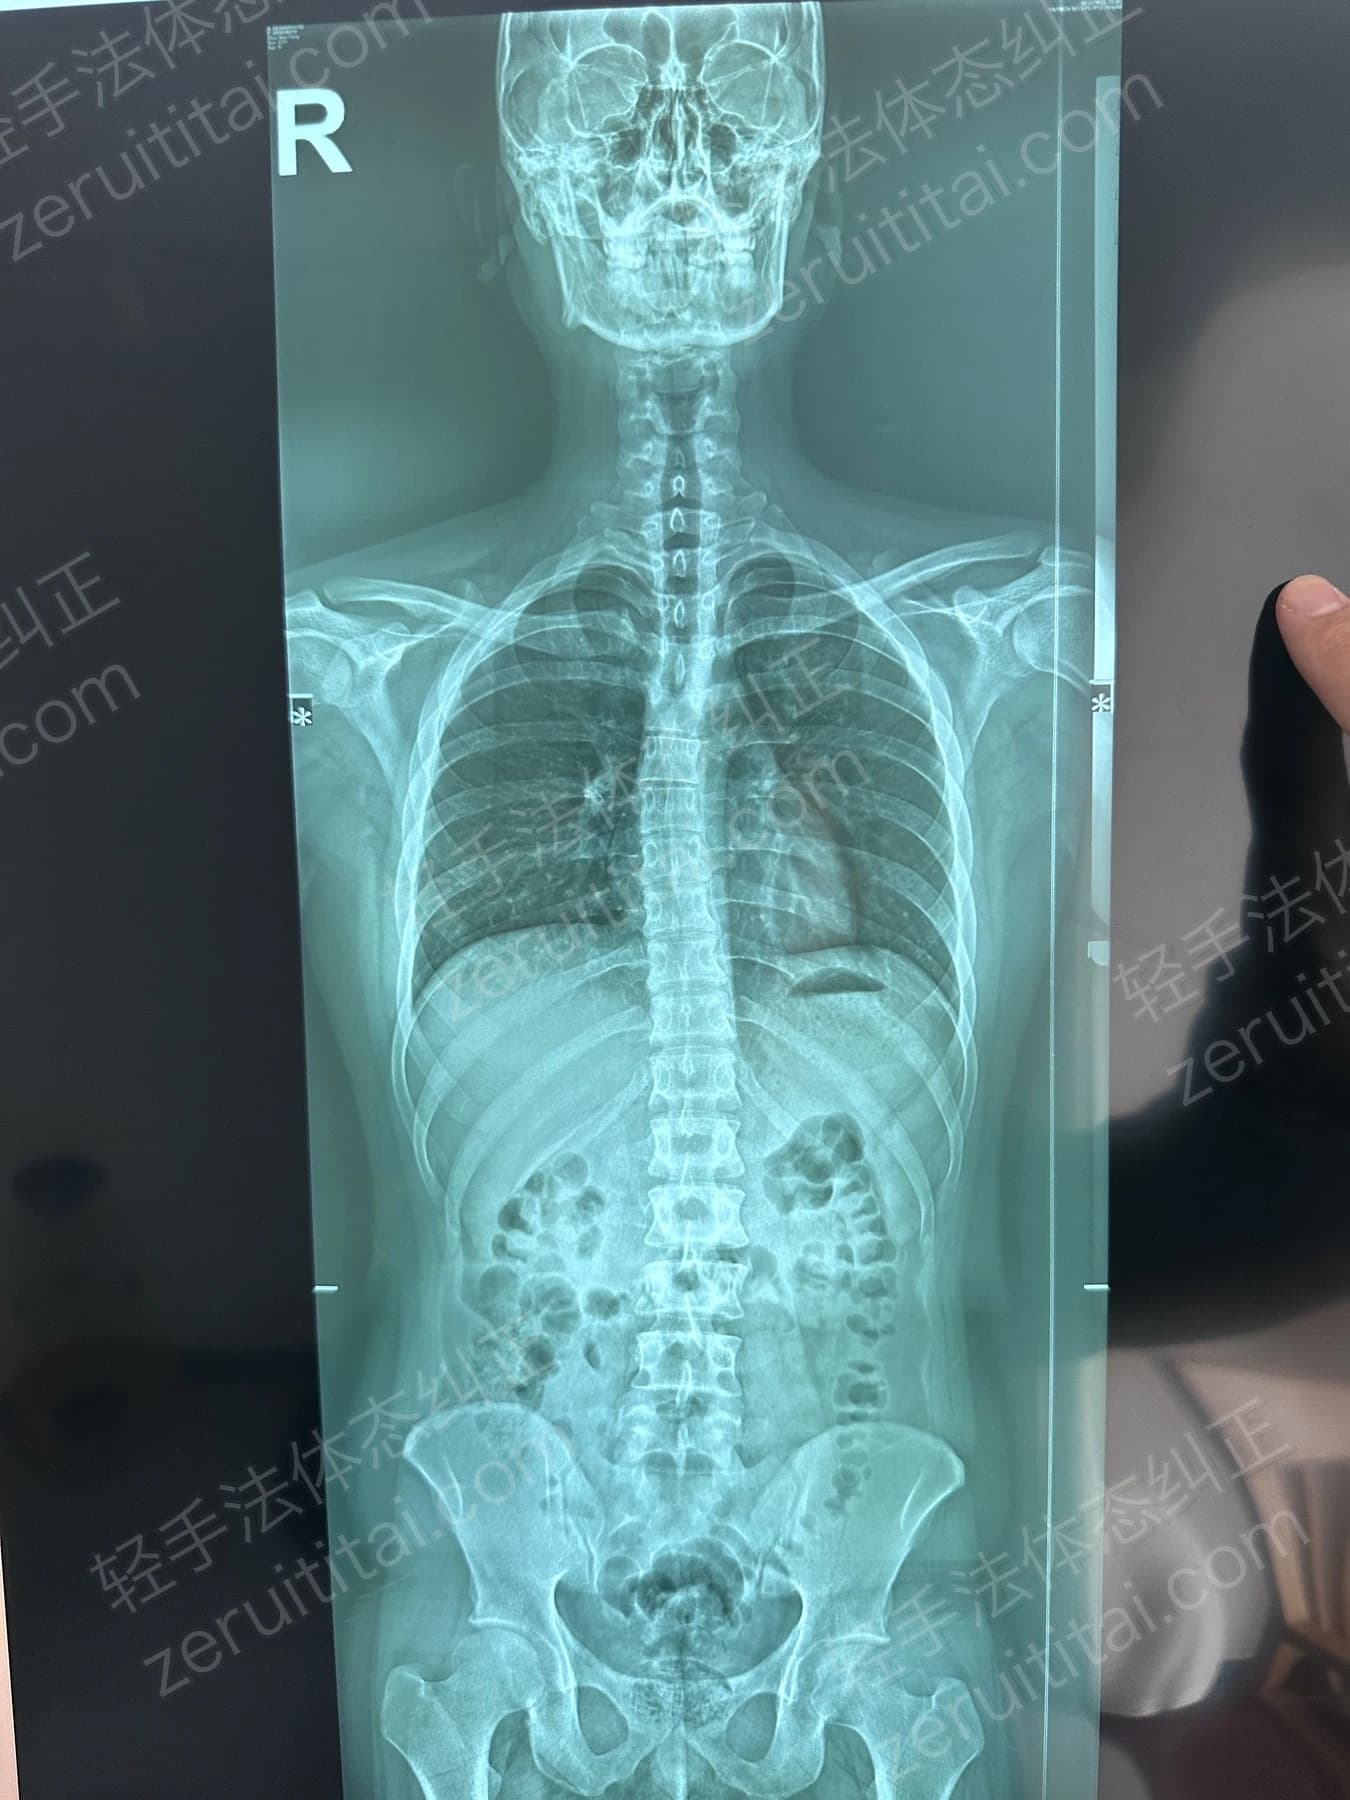

2022.06.27

第 1 次记录